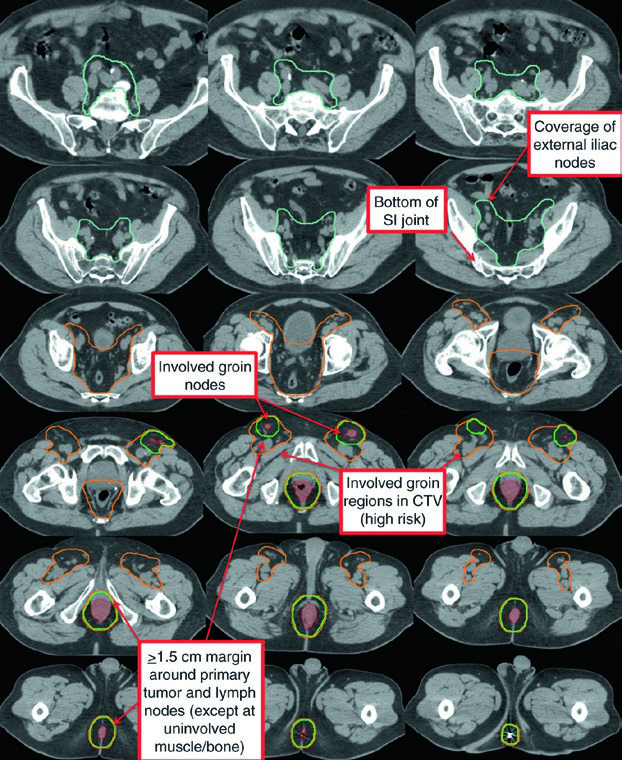

| CTV-P, CTV-N | CTV-P: GTV-P + 1.5–2.5 cm margin excluding uninvolved bone, muscle, or air. CTV-N: GTV-N + 1.0–1.5 cm excluding uninvolved bone, muscle, or air |

| CTV-HR (high risk) | Covers CTV-P, CTV-N, entire mesorectum, perirectal nodes, and bilateral internal iliac nodes inferior to the inferior border of the sacroiliac joint. If inguinal or external iliac nodes are involved, include these regions. 0.7 cm margin around internal iliac vessels. 1.8 cm strip between external and internal iliac vessels for obturator nodes. 1–1.5 cm anteriorly into bladder |

| CTV-LR (low risk) | Covers uninvolved internal iliac nodes superior to the sacroiliac joint inferior border, plus uninvolved external iliac and inguinal nodes. Margins: 0.7 cm around internal iliac vessels; 1 cm anterolateral on external iliacs; entire inguinal compartment contoured |

Contouring Atlas: Elective Nodal Regions

The RTOG anorectal contouring atlas describes three CTV regions that should be included for all patients with anal canal cancer. The Australasian GI Trials Group Atlas details seven elective regions. There is disagreement among the RTOG, AGITG, and BNG guidelines regarding inguinal lymph node contouring — recent data show that 10–29% of involved inguinal nodes fall outside the recommended nodal borders.

The T2N0 case demonstrates definitive chemoradiotherapy with IMRT: PTV-LR and PTV-HR treated simultaneously to 40 Gy (1.6 Gy/fraction) and 45 Gy (1.8 Gy/fraction) in 25 fractions, respectively. Then PTV-P received a sequential boost to 50.4 Gy (1.8 Gy/fraction) in 28 total fractions.

The T3N1a case with bilateral inguinal involvement had PTV-LR and PTV-HR treated simultaneously to 40 Gy and 45 Gy in 25 fractions. The bilateral inguinal and external iliac nodes were included in CTV-HR due to bilateral inguinal involvement. PTV-P and PTV-N then received a sequential boost to 54 Gy in 30 total fractions.